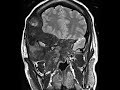

Fibrous Dysplasia-MRI

These images show a large extensive heterogeneously enhancing expansile osseous lesion which crosses sutures and involves the right frontal and temporal calvarium, bony orbit, right ethmoid, and maxillary sinuses resulting in severe facial deformity and marked right proptosis. The involved sinuses and mastoid air cells are obliterated. This heterogeneous appearance and enhancement on MRI can be potentially misleading to think of more aggressive neoplasms. Many times the CT appearance of ground-glass opacity helps to cinch the diagnosis of craniofacial fibrous dysplasia. The patient may develop symptoms related to cranial nerve palsies from narrowing of the skull base foramina.